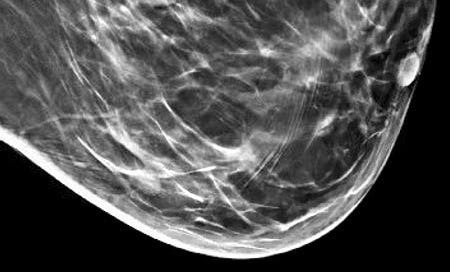

Grossly, the tumors are usually 2 - 5 cm, well circumscribed, soft to firm, lobulated masses. Although they appear sharply demarcated from surrounding tissue, they lack a true capsule and may exhibit pushing, expansile borders without widespread stromal invasion.

Medullary carcinoma - radiologic and microscopic images